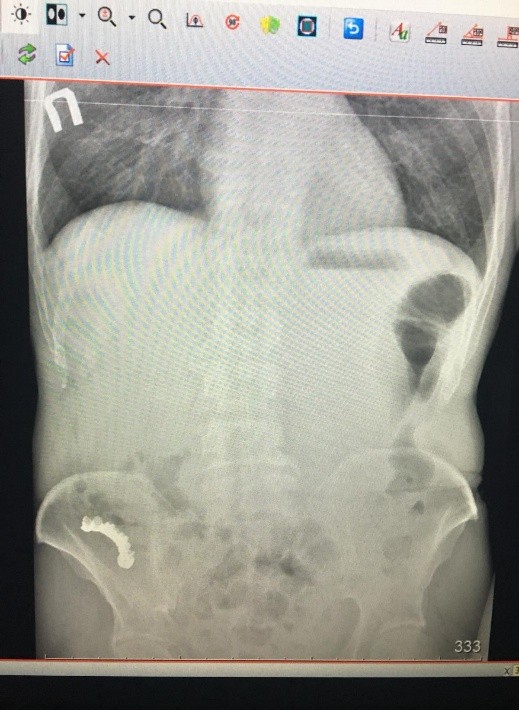

Диагностика рентгенпозитивных инородных тел успешно проводится с помощью традиционной рентгенографии и ультразвукового исследования (УЗИ) .

Рентген -диагностика.

Выявляется:

- дополнительная тень в зоне интереса;

- свободный газ в брюшной полости при перфорации полого органа;

- гипераэрированные петли кишечника с горизонтальными уровнями содержимого при развитии кишечной непроходимости.

- целесообразно использование хирургического материала рентгеноконтрастными метками, что облегчает их обнаружение при лучевой диагностике.